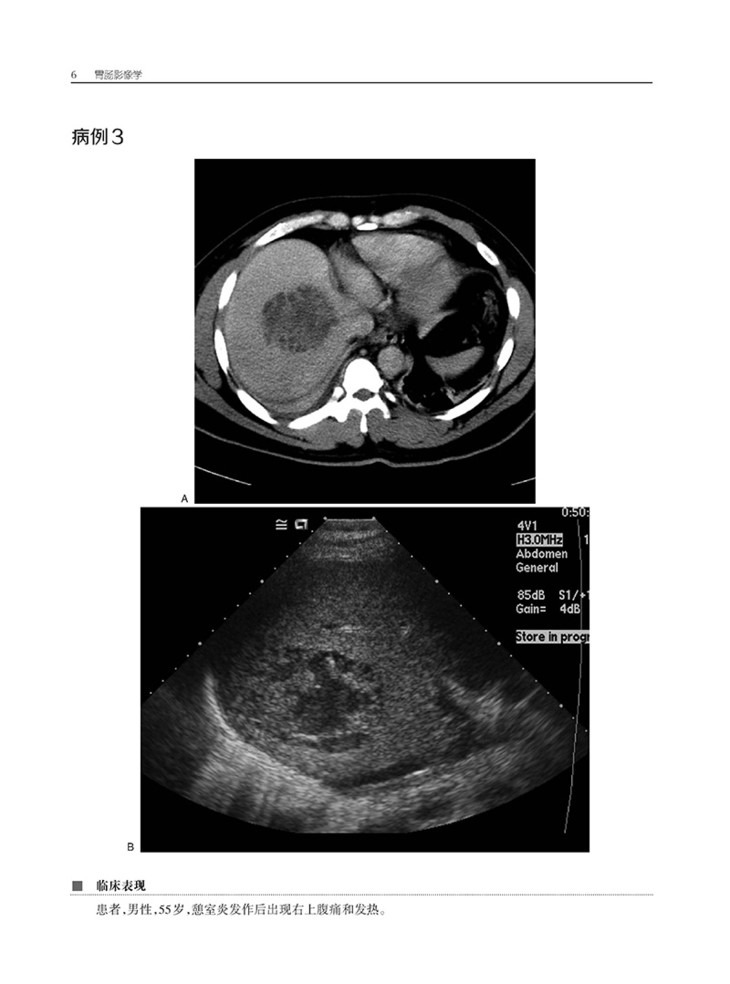

本书是“放射成像典型病例解析丛书”的分册之一,系统总结了100种典型腹部病例影像学诊断知识点,囊括了肝细胞癌、肝脓肿、肝硬化等常见疾病,以及肝血管平滑肌脂肪瘤和肝淋巴瘤等罕见疾病。全书从典型病例图像出发,从传统的X线检查到CT、MRI等更复杂模式的腹部成像,详细地展现了日常工作中遇到的胃肠道系统病变,对每一个病例的临床表现、影像学特征、鉴别诊断、相关知识点,以及经验和教训进行了分析总结,并针对每个病例精心设置了相关问题及其答案解析,可以帮助临床放射科医生及放射学相关专业的医学生强化专业概念,提高诊断技能。